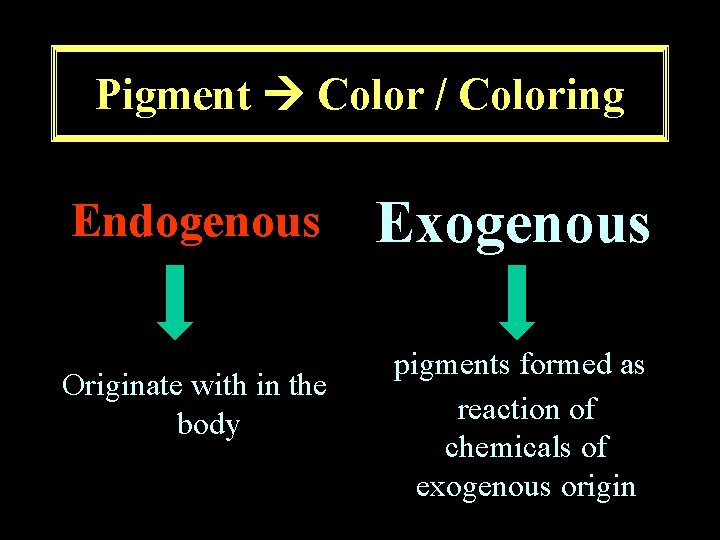

Pigment Color / Coloring Endogenous Originate with in the body Exogenous pigments formed as reaction of chemicals of exogenous origin